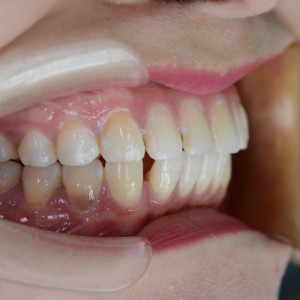

術(shù)前